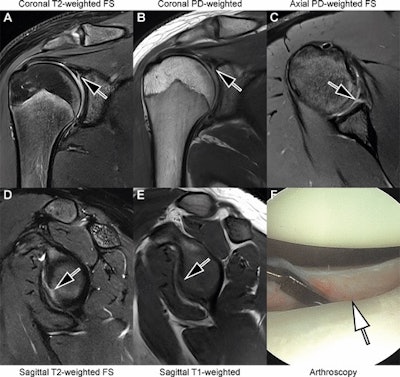

Images in an 18-year-old man with recurrent dislocations of the right shoulder. (A, B) Unenhanced coronal, (C) axial, and (D, E) sagittal deep learning super-resolution threefold parallel imaging -- accelerated turbo spin-echo MRI scans were obtained at 3-tesla field strength. (A) Coronal T2-weighted fat-suppressed (FS) and (B) coronal proton density (PD)-weighted MRI scans show a nondisplaced superior labral tear (arrows). (C) Axial proton density-weighted fat-suppressed, (D) sagittal T2-weighted fat-suppressed, and (E) sagittal T1-weighted MRI scans show continuation into a nondisplaced anteroinferior labral tear (arrows). All seven readers correctly diagnosed the arthroscopy-validated findings. (F) An arthroscopic photograph shows the anteroinferior labral tear (arrow). Image and caption courtesy of the RSNA.

For instance, the scans allowed the readers to correctly categorize the supraspinatus-infraspinatus tendons as normal versus partial-thickness tear versus full-thickness tear with a sensitivity of 89%, a specificity of 90%, and an accuracy of 89%. They also achieved a sensitivity of 93%, a specificity of 73%, and an accuracy of 86% for diagnosing tears of the superior labrum.